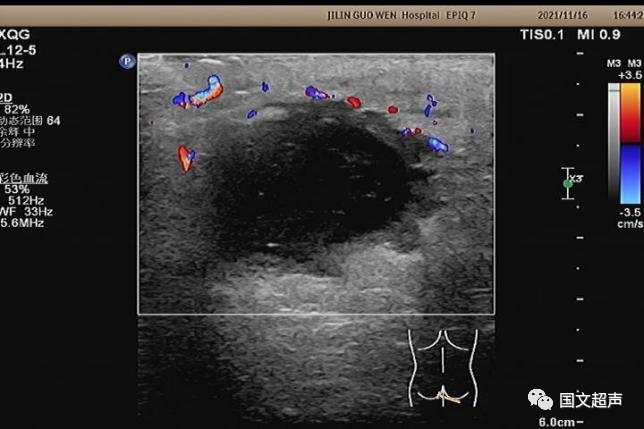

超聲檢查所見:

肛周:7點(diǎn)鐘方向皮下脂肪層內(nèi)探及不均質(zhì)低無回聲包塊,范圍約4.6*3.0cm,較淺處距體表約0.6cm,邊界不清,周圍軟組織回聲增強(qiáng),CDFI:周邊血流信號(hào)豐富,輕加壓探頭有涌動(dòng)感,如下圖: